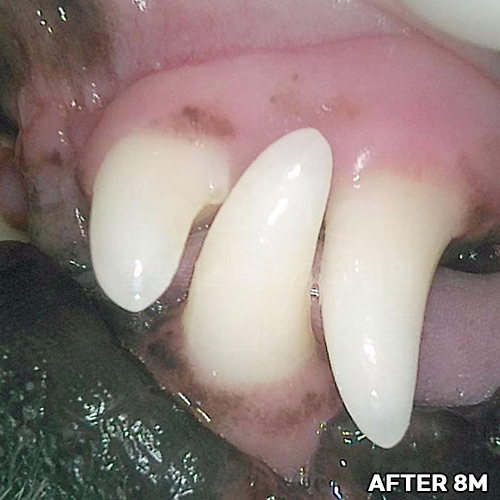

[강아지 치주치료 후 8개월 경과]